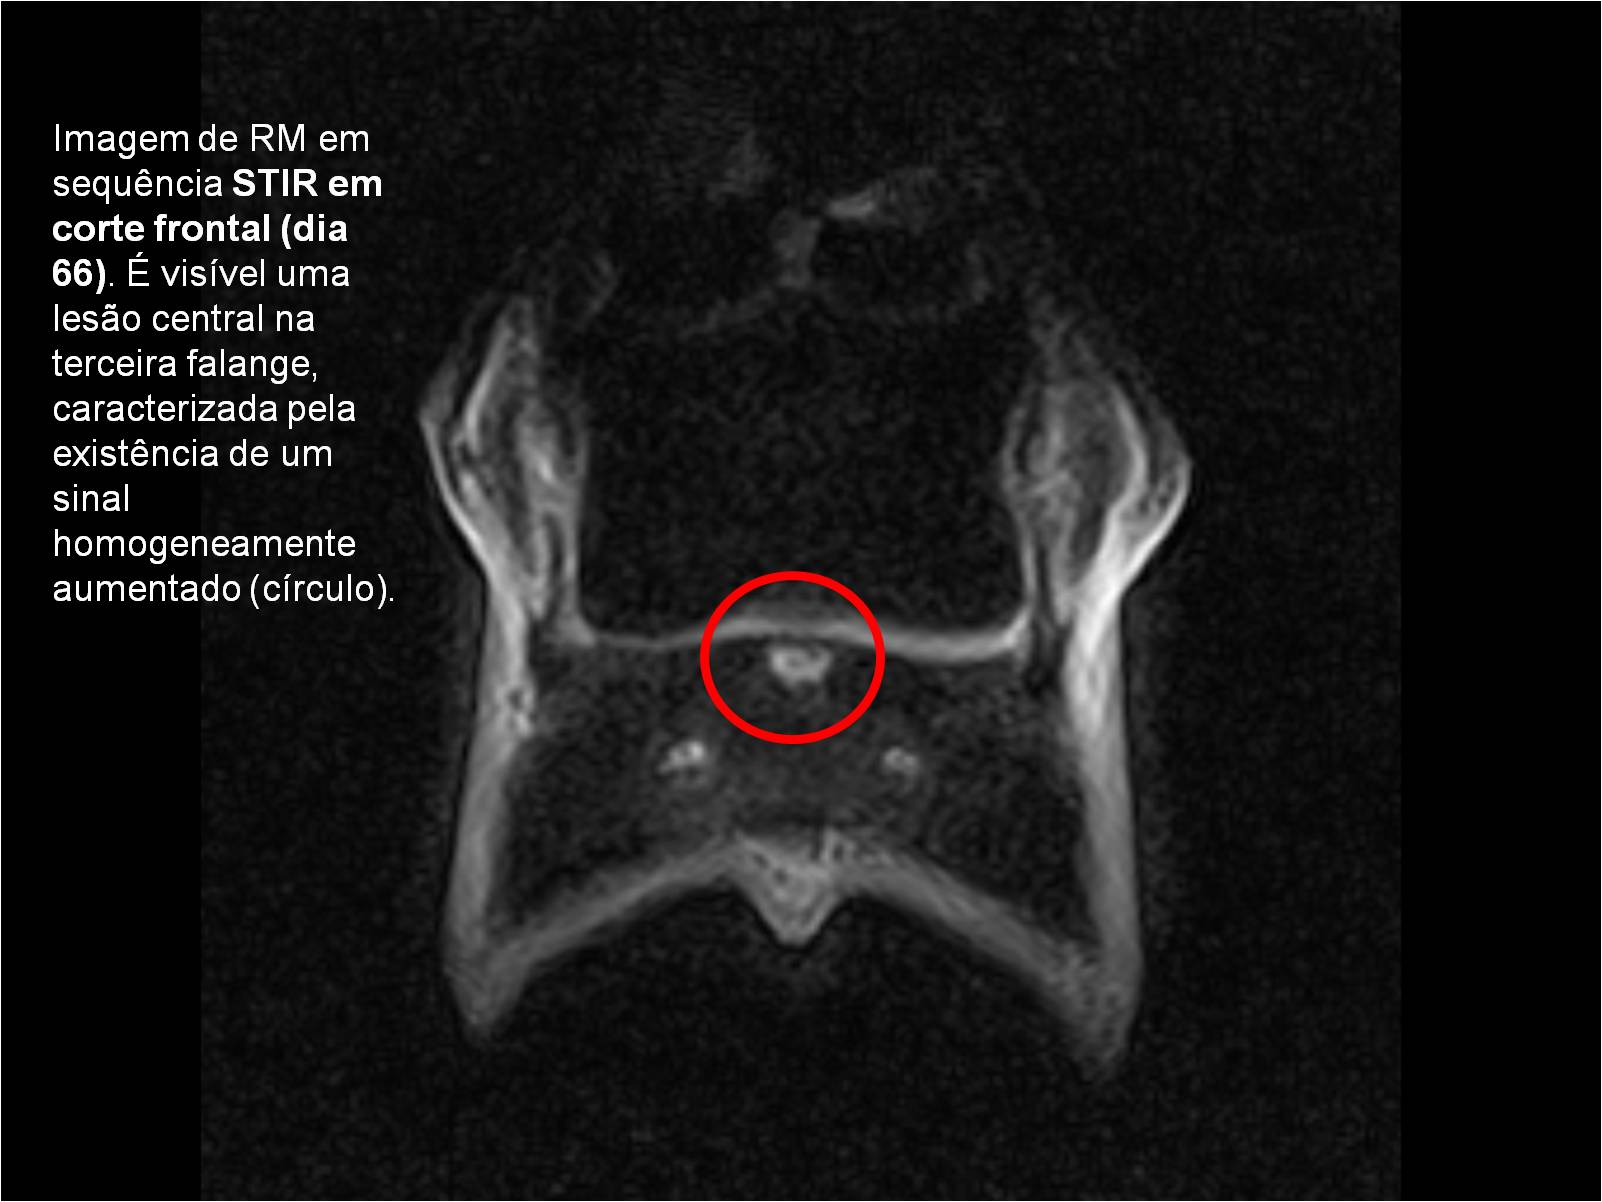

Publisher: Universidade de Évora

Abstract: O relatório de estágio encontra-se estruturado em três partes distintas. A primeira parte faz a caracterização das infraestruturas e funcionamento do Hospital Veterinário de Equinos de Lüsche, Oldenburg, Alemanha, assim como a análise casuística dos casos clínicos acompanhados durante os 6 meses de estágio. A segunda parte consiste de uma revisão bibliográfica sobre quistos do osso subcondral em equinos. Por fim, a terceira parte consta da apresentação e discussão de um caso clínico, nomeadamente o diagnóstico e acompanhamento imagiológico, por ressonância magnética, de um quisto subcondral na terceira falange num cavalo adulto; ### Abstract Equine Practice- Subcondral bone cyst of the third phalanx This internship report is divided in three parts. The first part characterizes the infrastructure and function of the Equine Hospital Lüsche, Oldenburg, Germany, as well as the casuistic of the clinical cases accompanied during the 6 month internship. The second part consists in a bibliographic review of cystic lesions of the subchondral bone in equines. The third part consists in a case report, the diagnostic and imagiological accompaniment, by use of magnetic resonance imaging, of a subchondral bone cyst in the distal phalanx of an adult equine.